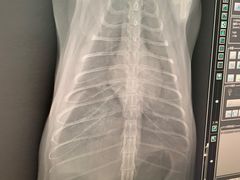

• 爱侣宠医·鹦鹉专科·小型哺乳类·异宠专科(灵石路店)

• -爱侣宠医·鹦鹉专科·小型哺乳类·异宠专科(灵石路店)